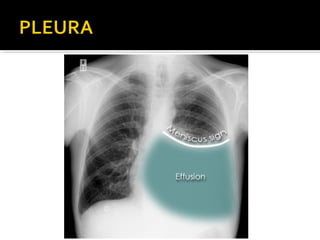

Este documento fornece parâmetros técnicos para realizar uma radiografia de tórax, incluindo posicionamento correto do paciente, dose adequada de radiação e estruturas anatômicas a serem avaliadas, como coração, pulmões, pleura, diafragma e ossos do tórax.